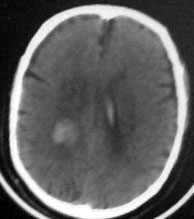

病人男性52岁,一年前曾患脑出血.今突发剧烈头痛,恶心,呕吐..病人家属说病人自去年脑出血以后,精神异常!请大家看看左侧颞叶病灶考虑什么?片子不是很清楚请大家见谅!!左颞叶病灶ct值最高处为85hu

左颞叶病灶我认为不是出血,就算是出血,也与右侧病灶性质不同。理由:1.该病灶密度较淡而不均匀,其间见斑点状更高密度。急性出血,应该不会是这个样子。

综合上诉特点,左颞叶病灶我首先考虑:avm。

左颞叶病灶考虑血管畸形,如果上次片子就有更支持此诊断。

1右丘脑脑出血破入脑室; 2左颞叶avm。如果去年有则更加证明是avm,如果去年没有则可能是钙化尚少,显示不明显. 建议强化

左侧颞叶病灶密度不均,似见点状钙化,支持血管畸形性病变.右侧病变为出血.